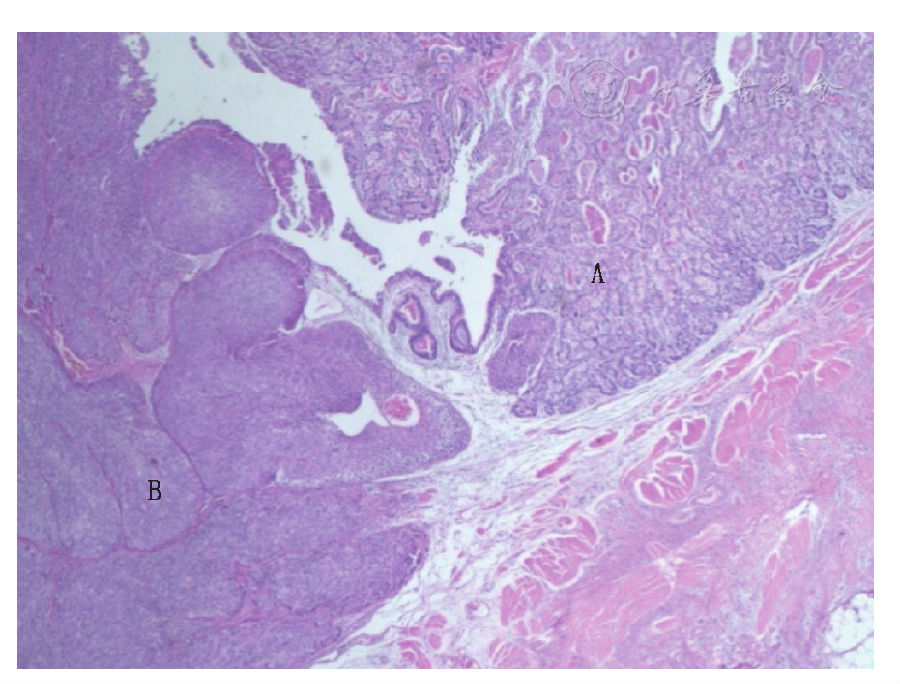

:肾脏大小10.0 cm×7.0 cm×4.5 cm,表面见多个小囊肿,内含澄清液,肾盂黏膜光滑,输尿管下端见一1.0 cm×1.0 cm×0.8 cm肿块,表面呈乳头状,切面灰白色,向腔内生长,广基。镜下观察见肿瘤分腺癌和尿路上皮癌两个不同的区域(图1),腺癌区域见大小不等的小管,部分为乳头状,肿瘤细胞形态为扁平、立方状、柱状,胞质透亮,可见鞋钉样细胞,细胞中度异形,核分裂象易见。

肿瘤分腺癌(A)和尿路上皮癌(B)两个不同区域

图1输尿管透明细胞腺癌伴尿路上皮癌病理图片(HE ×40)